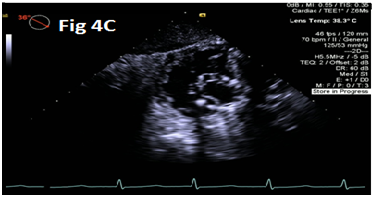

A 73-year-old female with mechanical mitral valve, tricuspid annuloplasty (32mm Edwards Physio Tricuspid incomplete ring) underwent Transcatheter Tricuspid Valve Replacement (TTVR) using off-label 29mm Edwards Sapien 3 (S3) Transcatheter Heart Valve (THV). Immediate post valve deployment, mild Perivalvular Leak (PVL) was noticed at the septal aspect (area of incomplete annuloplasty ring). Eighteen months later, patient presented with recurrent right heart failure and paracentesis due to severe tricuspid PVL (Figure 1A-C, Video 1). Percutaneous PVL closure under general anesthesia, Trans-esophageal Echocardiography (TEE) was performed. Via femoral venous access, defect was easily crossed with Agilis steerable sheath, multipurpose catheter and 0.035” glide wire. Despite recurrent attempts, wire came through the PVL but then traversed through open cells of S3 into the right ventricle (Figure 2A), confirmed with Armada 6mm balloon waist at the S3 cage (Figure 2B) (despite inflating 28mm Z med balloon inside S3 cage, Figure 2C). We decided to partially deploy the plug and assess valve function. Using 7.5F Asahi Eaucath multipurpose guide, a 12mm AmplatzerTM Vascular plug II (AVP II) was advanced through the defect. The ventricular disc was opened inside the S3 cage while body in the PVL defect (outside the S3 cage) and atrial disc on the atrial side of PVL (Figure 3A-B). With S3 function unaffected, no central leak and minimal gradient, PVL reduced to mild severity (Figure 4A-D, Video 2); the AVP II was successfully deployed (Figure 5). At 3-month follow up, there was an excellent symptomatic improvement (NYHA functional class I), with no heart failure re-hospitalization or paracentesis. Deployment of plug disc inside the valve frame is not recommended due to fear of interference with leaflet function and possible injury in long term. There was no immediate issue with the valve function in this case (due to space between the leaflet and frame of S3 and depends on size of plug used). Valve-in-Valve (S3-in-S3) would have certainly sealed all open cells treating this PVL but is more expensive option.

Figure 4 Post AmplatzerTM vascular plug II with mild residual PVL (4A), mildly elevated trans-S3 gradient (4B) and normal leaflet mobility of S3 (diastole 4C, Systole 4D).